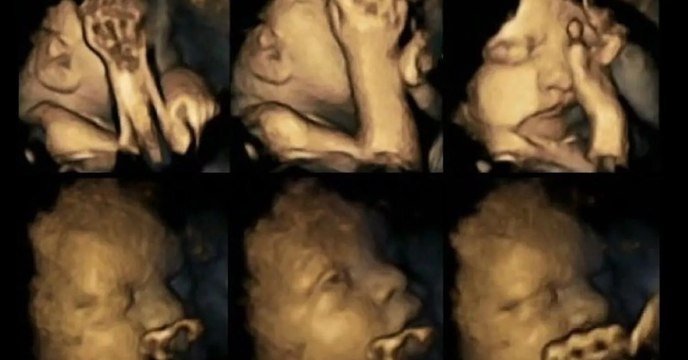

Erschreckende Bilder aus dem Mutterleib: So verhalten sich Föten, wenn die werdende Mutter raucht